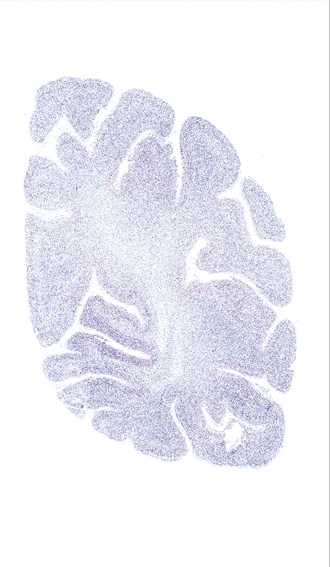

Hi-Resolution Sections · Cells (Nissl Staining) · Virtual Microscopy

Frontal sections (Nissl) from the Atlas Brain:

Microscopy

Slice ID:

r4-0920

Plate NR:

59

Position:

61,6 mm